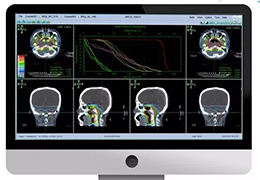

ART-Plan™ Artificial Intelligence Contouring